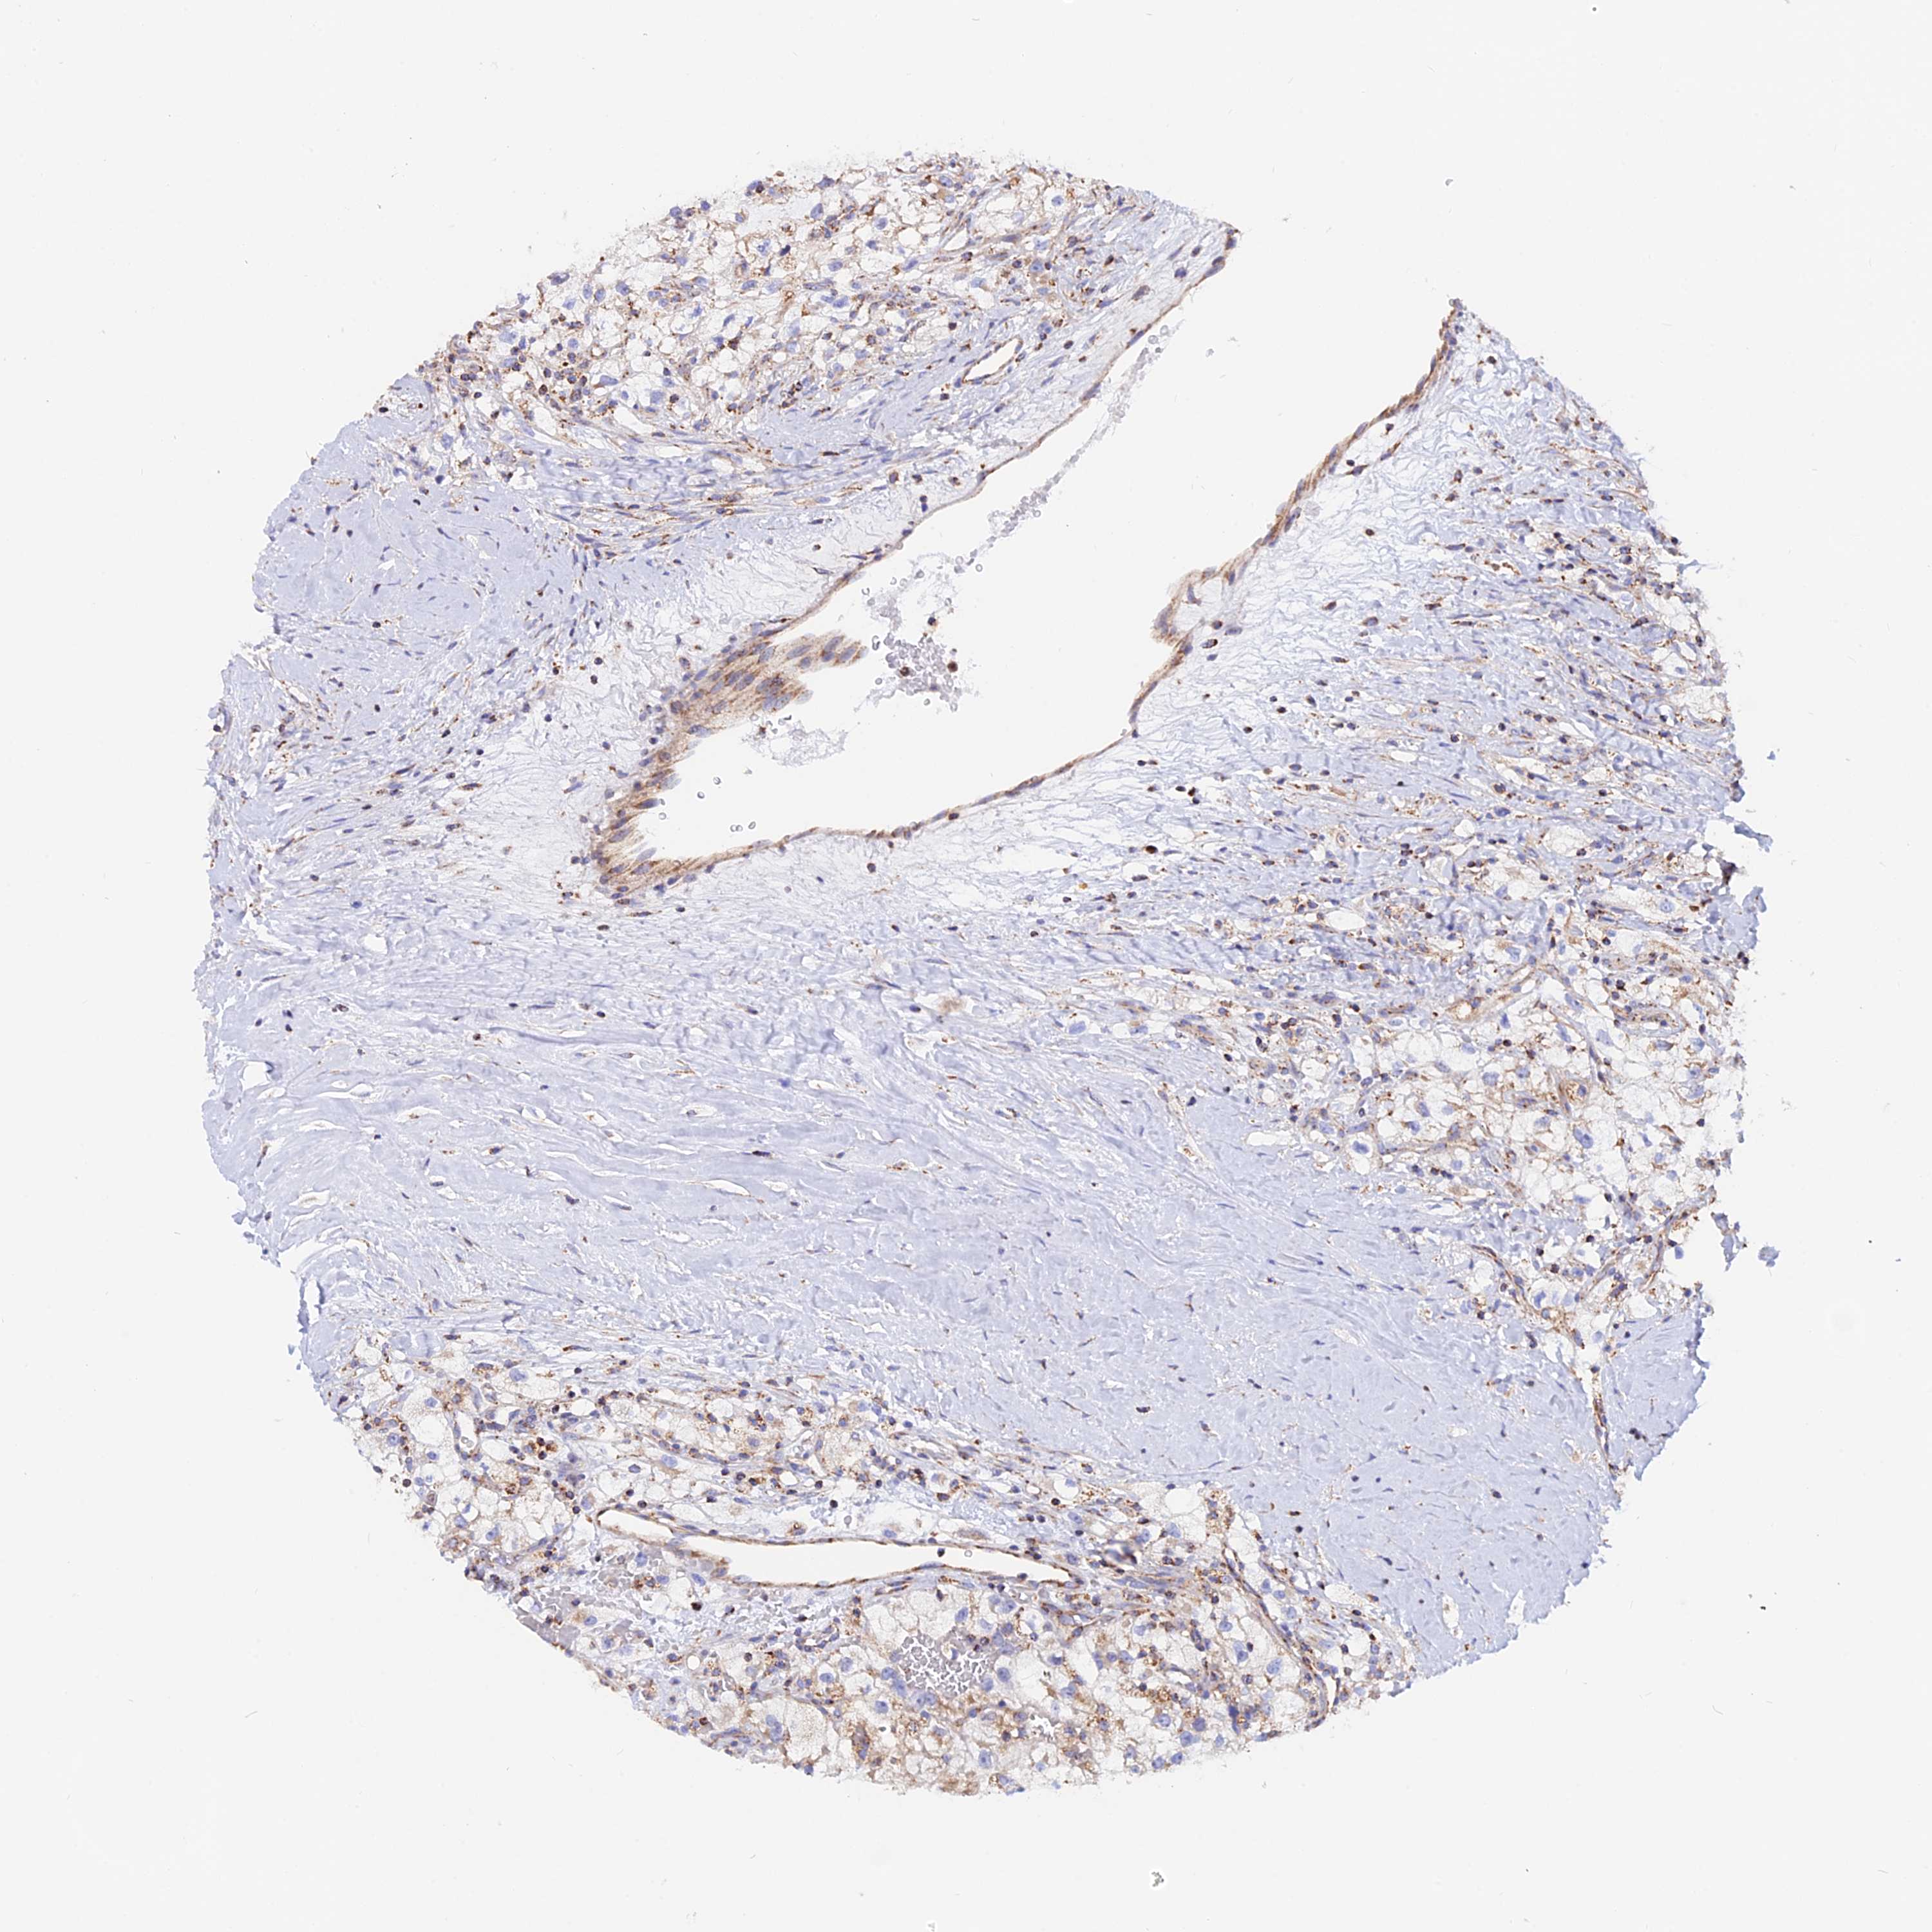

KIDNEY RENAL CLEAR CELL CARCINOMA (VALIDATION) - Interactive survival scatter ploti

The Survival Scatter plot shows the clinical status (i.e. dead or alive) for all individuals in the patient cohort, based on the same data that underlies the corresponding Kaplan-Meier plots. Patients that are alive at last time for follow-up are shown in blue and patients who have died during the study are shown in red.

The x-axis shows the expression levels (FPKM) of the investigated gene in the tumor tissue at the time of diagnosis. The y-axis shows the follow-up time after diagnosis (years). Both axes are complimented with kernel density curves demonstrating the data density over the axes. The top density plot shows the expression levels (FPKM) distribution among dead (red) and alive patients (blue). The right density plot shows the data density of the survived years of dead patients with high and low expression levels respectively, stratified using the cutoff indicated by the vertical dashed line through the Survival Scatter plot. This cutoff is automatically defined based on the FPKM cutoff that minimizes the p-score. The cutoff can be changed by dragging the vertical line or by entering a cutoff value in the square labeled "Current cut-off".

Under the Survival Scatter plot the p-score landscape (black curve; left axis) is shown together with dead median separation (red curve; right axis). Dead median separation is the difference in median mRNA expression between patients who have died with high and low expression, respectively. It is calculated as follows: median FPKM expression of dead patients with high expression - median FPKM expression of dead patients with low expression. This is intended to aid the user in visually exploring custom cutoffs and the associated p-scores and dead median separation.

Individual patient data is displayed and can be filtered by clicking on one or more of the category buttons on the top of the page. Categories describing expression level and patient information include: high, low, alive, dead, female, male and tumor stages. The scale of the x-axis can be toggled between linear and log-scale by clicking on the "x log" button. Mouse-over function shows TCGA ID, patient information and mRNA expression (FPKM) for each patient.

& Survival analysisi

Kaplan-Meier plots summarize results from analysis of correlation between mRNA expression level and patient survival. Patients were divided based on level of expression into one of the two groups "low" (under cut off) or "high" (over cut off). X-axis shows time for survival (years) and y-axis shows the probability of survival, where 1.0 corresponds to 100 percent.

GCDH is not prognostic in Kidney Renal Clear Cell Carcinoma (validation)

Best expression cut offi

Based on the FPKM value of each gene, patients were classified into two groups and association between prognosis (survival) and gene expression (FPKM) was examined. The best expression cut-off refers the FPKM value that yields maximal difference with regard to survival between the two groups at the lowest log-rank P-value. Best expression cut-off was selected based on survival analysis .

When clicking on this number, the vertical dashed line indicating cut-off, the interactive survival plot, and the Kaplan-Meier curve will be adjusted to show results based on the best expression cut-off.

: 13.71

Median expressioni

Median expression refers to the median FPKM value calculated based on the gene expression (FPKM) data from all patients in this dataset. When clicking on this number, the vertical dashed line indicating cut-off, the interactive survival plot, and the Kaplan-Meier curve will be adjusted to show results based on the median expression.

: N/A

Median follow up timei

Median follow up time refers to the median time (years) after diagnosis with this type of cancer, based on clinical data from all patients in this dataset.

P scorei

Log-rank P value for Kaplan-Meier plot showing results from analysis of correlation between mRNA expression level and patient survival.

N/A

5-year survival highi

5-year survival for patients with higher expression than the expression cutoff.

For melanoma and glioma, 3-year survival is shown.

5-year survival lowi

5-year survival for patients with lower expression than the expression cutoff.

TCGA RNA samplesi

RNA-seq data is reported as average FPKM (number Fragments Per Kilobase of exon per Million reads), generated by the The Cancer Genome Atlas (TCGA) .

Normal distribution across the dataset is visualized with box plots, shown as median and 25th and 75th percentiles. Points are displayed as outliers if they are above or below 1.5 times the interquartile range. FPKM values of the individual samples are presented next to the box plot.

Average pTPM 14.5

Number of samples 100